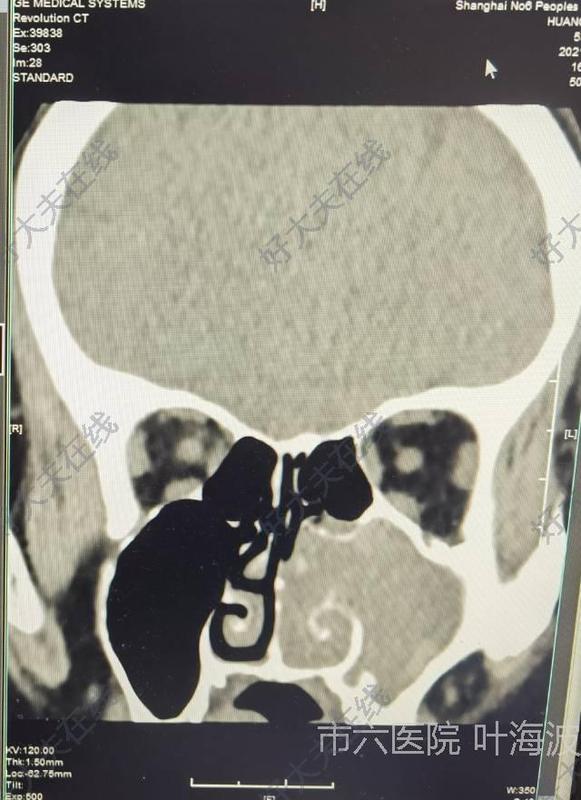

治療前左側(cè)鼻塞流涕3月入院,電子鼻咽鏡和CT發(fā)現(xiàn)鼻腔內(nèi)發(fā)現(xiàn)鼻腔鼻竇內(nèi)有腫物,并有霉菌團(tuán)塊信號(hào)影治療后治療后150天術(shù)中證實(shí)鼻竇內(nèi)翻性乳頭狀瘤和霉菌團(tuán)塊。術(shù)后鼻塞流涕癥狀消失,術(shù)后5月復(fù)查MRI鼻腔鼻竇腫瘤病灶完全清除,沒(méi)有復(fù)發(fā)。